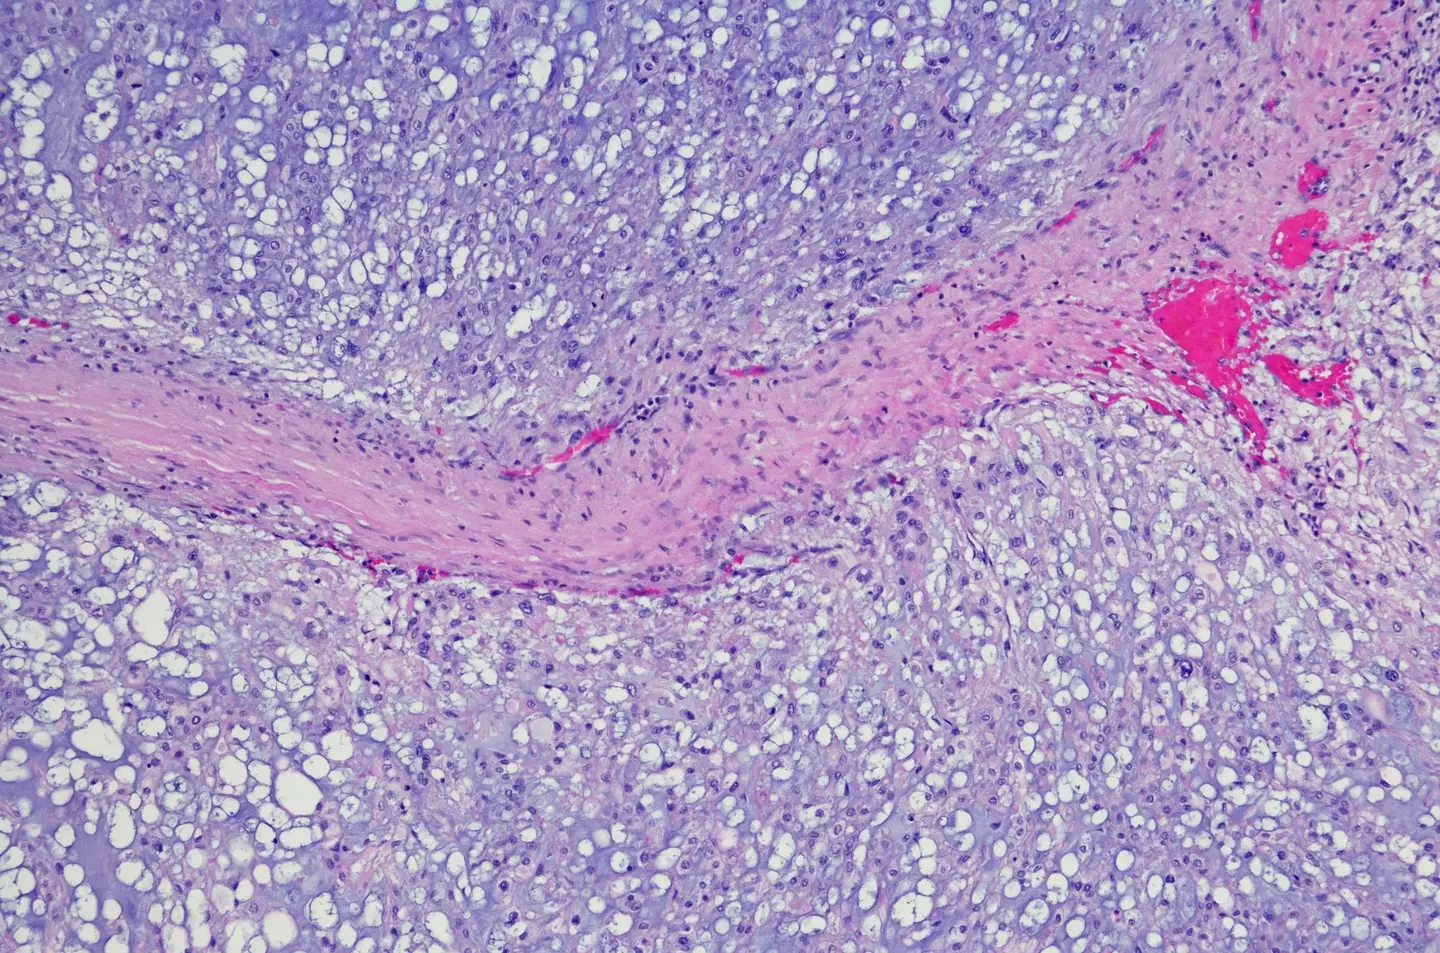

According to Cancer Research UK, chordoma is a rare and slow growing type of primary bone cancer, typically found in either the bottom of the spine or near the base of the skull. Globally, one in 1,000,000 people per year are diagnosed with chordoma.

Current research suggests that chordomas are caused during the development of a baby's spine in the womb in which the notochord, a precursor to the spine, is replaced by bone. However, in some adults notochord cells may remain, which scientists believe cause chordoma.

Put simply, researchers previously found that brachyury is 'essential' to the growth of chordoma tumours and has for years been 'considered undruggable' by scientists.